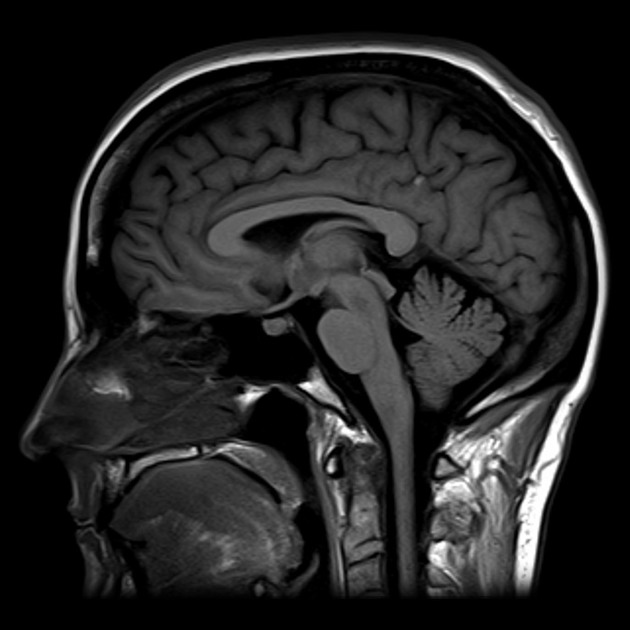

I’m describing a medical procedure known as an MRI, which stands for Magnetic Resonant Imaging. In my case, a recent trip in this machine was to scan my neck and my brain, to help determine the cause of body inflammation that I’ve been experiencing for some time. There’s also the possibility that I have something known as “Hyperreflexia,” a condition where my body’s reflexes are over-responsive. I’m not sure how the two illnesses (?) are connected, but hopefully, that will be determined in a follow-up appointment.

In the MRI machine, there’s a plastic vice that your head goes in, there’s a moving platform that you are placed on, and a projected screen saver that plays on shuffle/repeats on the inside of the tube, right above your face. The earplugs go in, the soft and soothing music turns on, and the machine begins its job. For one hour, I stared at pictures of outer space, as loud cranks and alarms went off all around me. For the first phase of the procedure, I went in as I was. For the second phase, I was injected with a somewhat radioactive dye that would make my internal systems look much clearer. Talk about glowing.